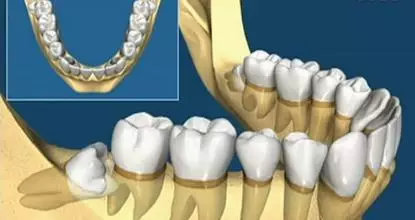

▲智齿的各种生长状态

看看上图这些智齿的生长位置,真是千奇百怪。智齿但一旦生长位置出现了偏差,那就得科普另外一个词,阻生齿。